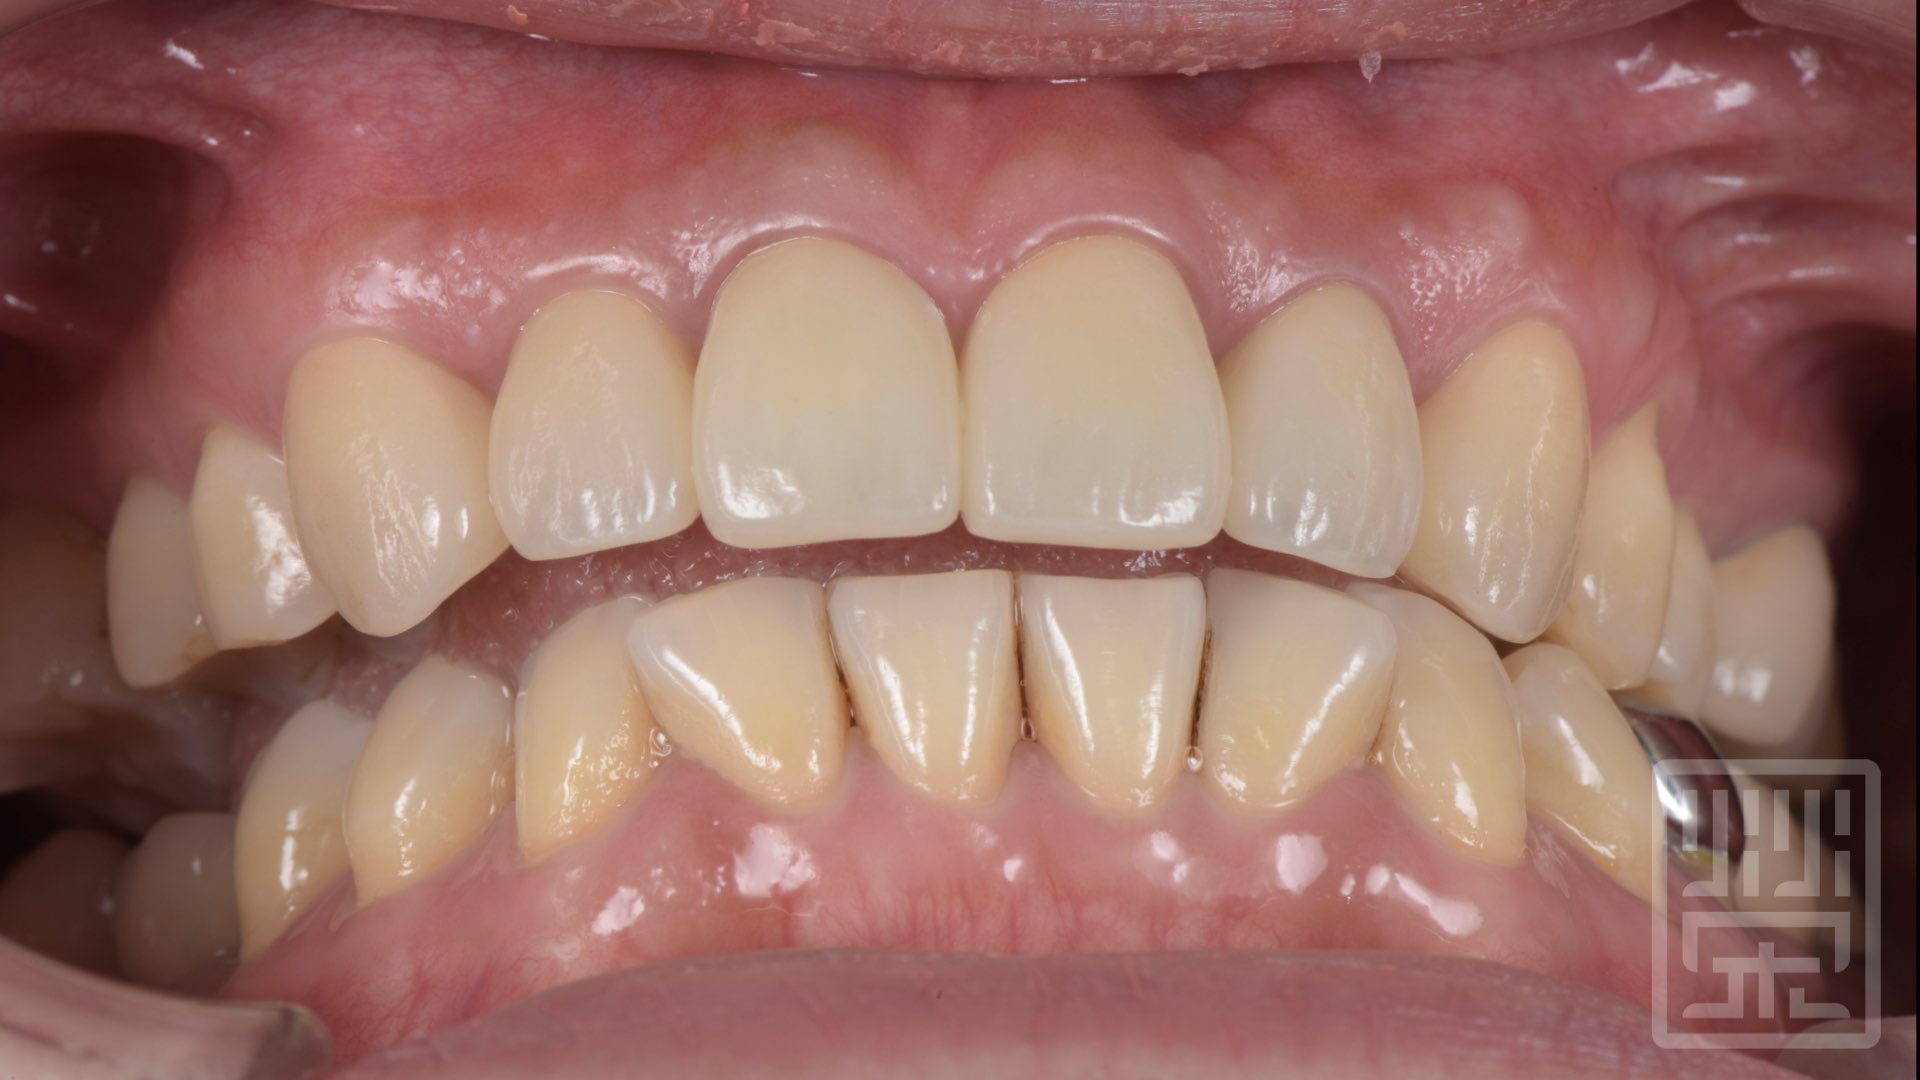

保護性咬合